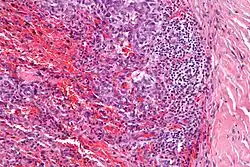

Micrograph showing an angiomatoid fibrous histiocytoma. H&E stain.

It is characterized by cystic blood-filled spaces and composed of histiocyte-like cells. A lymphocytic cuff is common. It often simulates a vascular lesion, and was initially described as doing this.[1]